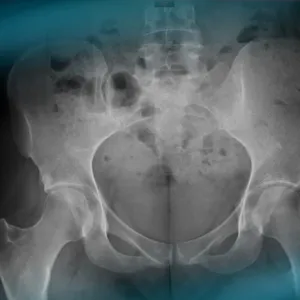

The goals of this clinical case are to discuss the different therapeutic options in the case of a 30-year-old woman with hip pain despite having had hip arthroscopy.